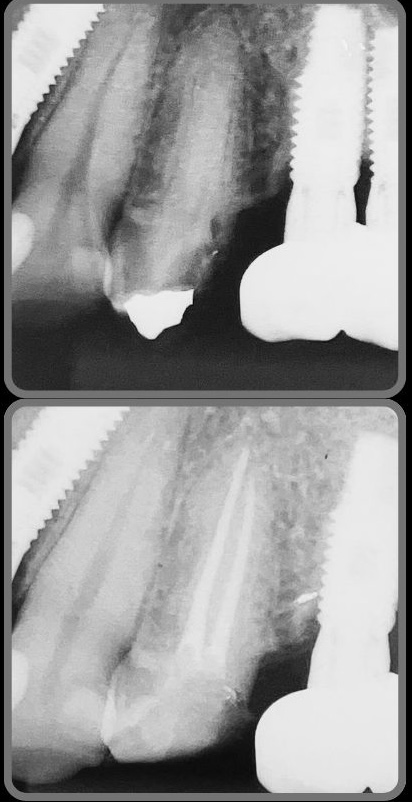

Veja alguns casos de sucesso